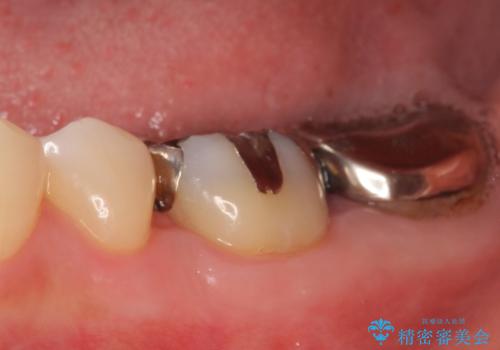

- 左下奥歯で咬むと違和感があるといらっしゃった方の症例です。

検査の結果左下7は失活(歯の神経が死んでいること)しておりX線上で根尖病変を認めたため、根管治療を行いました。

また左下6は遠心にあった歯茎より深い虫歯(縁下カリエス)の問題を解決するため、歯茎を下げる歯周外科手術を行いました。